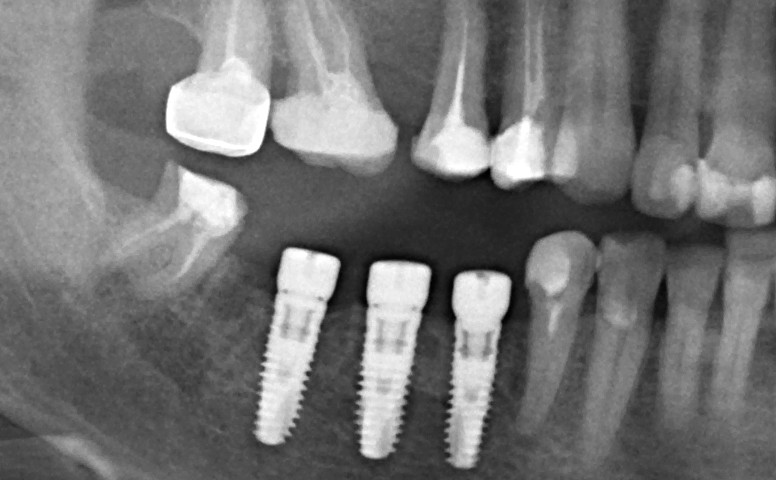

Остеопластика или «наращивание костной ткани» при имплантации — выбор метода и отдаленные результаты.